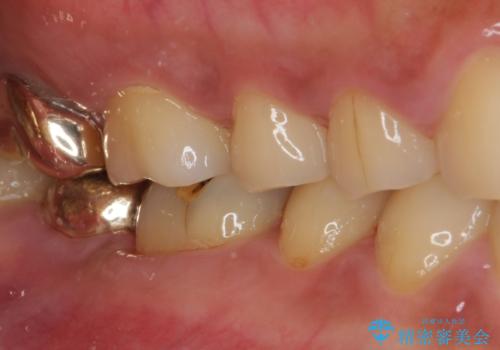

ゴールドインレーは銀歯のインレーやセラミックインレーと比べ、「技工操作の精度が高く、適合が著しく良い」というメリットがあります。特に上の奥歯は歯科医師の操作が行いにくいため、「適合の良さ」は再治療のリスクを防ぐ上でとても重要な要素となります。

上の奥歯は金属色が見えることもないため、審美的な問題は全くありません。

咬み心地はとても良好で、全く違和感がなく、患者様には大変満足していただきました。